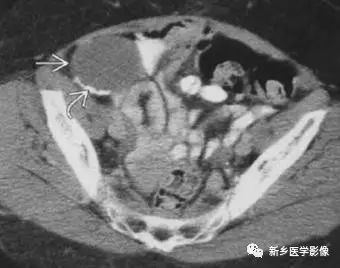

主要位于盆腔内,表现为不均一的点状钙化

主要表现为盆腔内对称性小钙化灶。